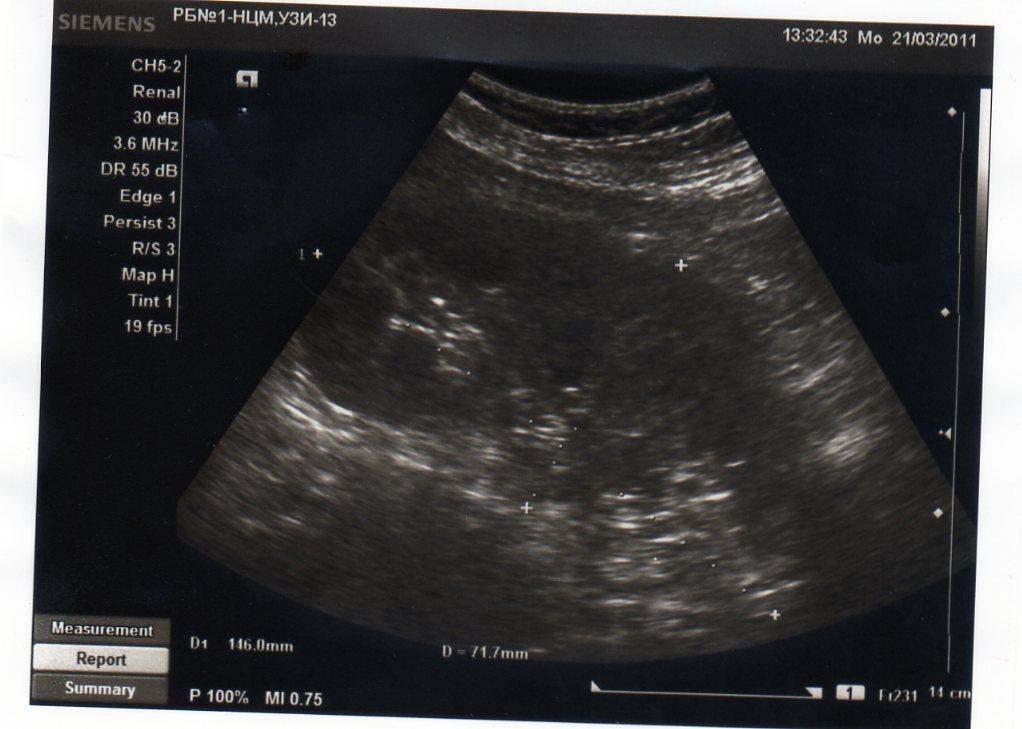

2 года назад у меня обнаружили кисту почки. в этом году УЗИ показала,что она исчезла. У меня одна единственная почка размером 146*71, увеличена. Киста размером 2,8*3,8 мм.сейчас почки болят.